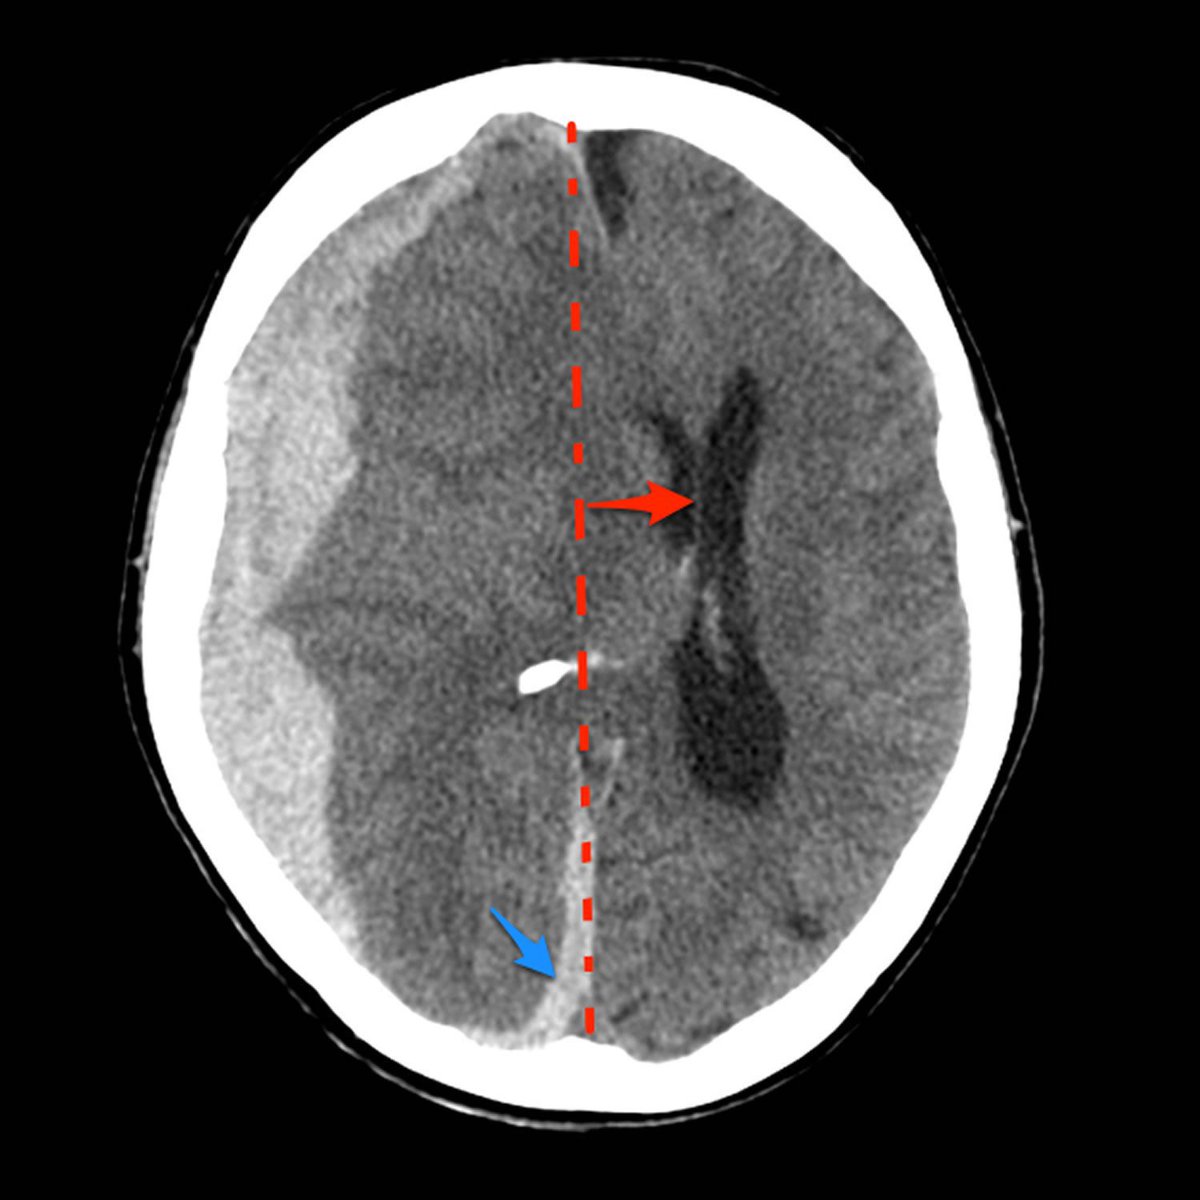

الحرف الثالث هو ال “B”

ونقصد فيه الBrain

لازم نتأكد من عدم وجود:

1) Midline shift / herniation

2) loss of Grey-white matter differentiation

وحدة من علامات الستروك "early sign”

3)brain atrophy

4)Hypo/hyper dense areas